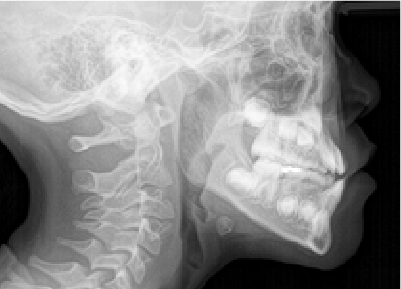

バイオブロック矯正とは

下方成長の症例のbefore/after

発達に寄り添いながら、

正しい成長を促す

バイオブロック矯正は、歯だけではなく顔全体の発達に焦点を当てた矯正治療法です。顎の下方成長(顎が下へ下がるように発達すること)を防ぐことに重点を置き、正しい方向への成長を促します。顎が正しく発達することで、永久歯が生える前に、生えやすい場所に移動するため、治療期間の短縮につながります。

取り外し可能な器具を使用して顎や歯の位置を正しい向きに調整し、より自然な方法で歯並びを整えることを目指します。

主要な治療内容と効果:顎の成長のコントロール

バイオブロック矯正では、顎の成長を前方へ導き、下顎の後退を防ぎます。

歯並びだけを整えるのではなく、すべての歯が自然な位置で並ぶことができる顎を目指します。

これは、成長過程だからこそできる治療法です。歯並びが崩れにくい顎をつくることで、問題の根本解決につながる上に後戻りしにくく、矯正後のケアも少なく済みます。